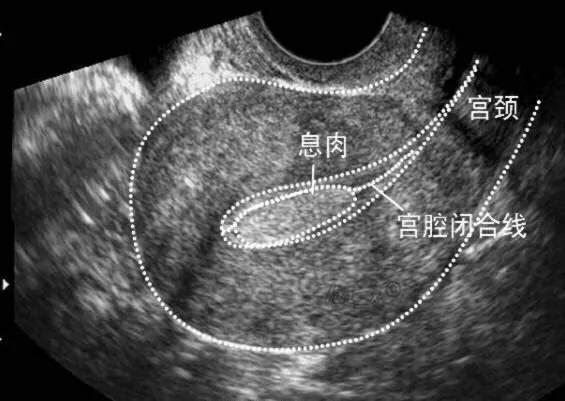

在很多月经不调、不孕症的疾病中,可以看到也值得深入评估子宫内膜容受性。比如:多囊卵巢综合征、黄体功能不够、子宫内膜异位症、子宫内膜息肉、卵巢功能减退、免疫问题等等。

2.子宫内膜异位症、内膜息肉、内膜增生过厚。实际上是相同的机制,连续而各有特点的具体表现。这些问题突出表现为雌激素偏高,或绝对值不高而相对偏高,持续黄体功能欠佳引起的孕、雄激素效应弱,无力对抗协调雌激素。不少患者在月经刚干净后内膜还是偏厚。易出现盆腔瘀血综合征、经前期头痛、腹部腰部酸胀痛、口腔溃疡、情绪差。直接引起在黄体期内膜转化不够,质地差,容受性差。